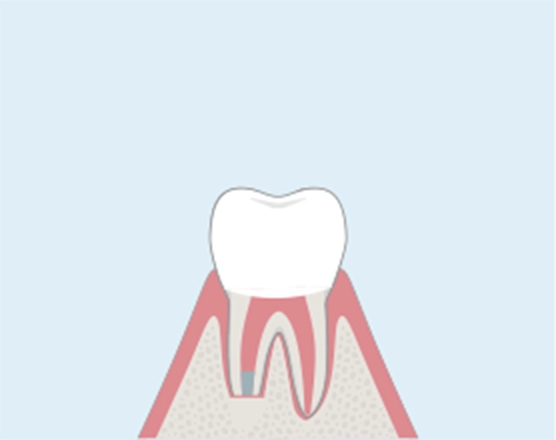

CASE 01

病巣が歯の根の先にある場合

歯根端切除術

根管治療を行っても予後不良として、歯の根の先に感染が進み膿がたまるなど、強い痛みや炎症が起こることを「根尖病巣」や「歯根嚢胞」と呼びます。根管治療による再治療が難しい場合は抜歯に至りますが、歯根端切除術では歯の根の先端を切除することで、抜歯を避けることが可能になります。

01

歯の根の先に膿がたまった状態。

-

02

歯茎側から病巣を切除する。

03

病巣を切除し、MTAセメント(殺菌する薬剤)を詰める。

04

縫合する。治療後、骨は自然に再生します。